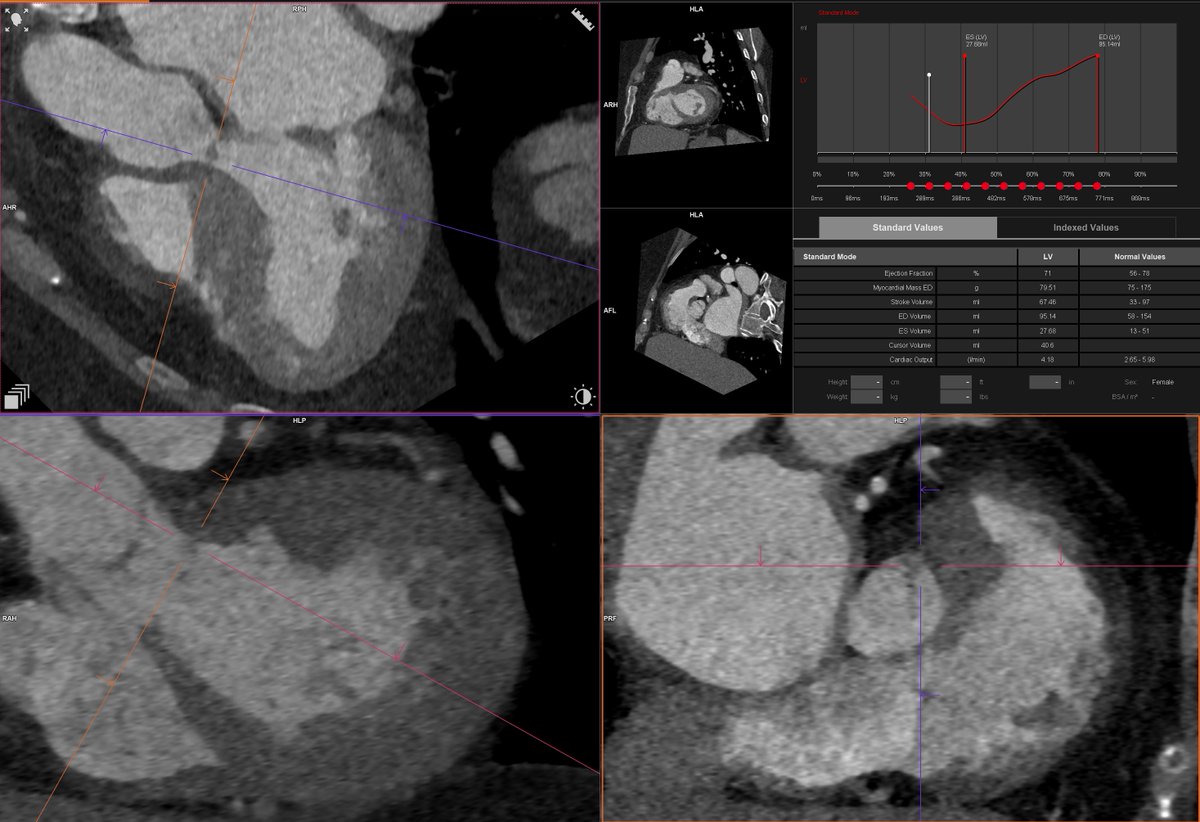

Shone's complex, parachute MV with single papillary muscle attachement (video), subaortic membrane (still) #YesCCT @Heart_SCCT